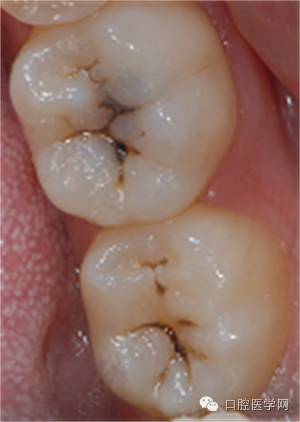

前后对比

术前

术后

小结:

1 对于一部分牙合面形态完整的病例,印章法是很好的充填方式,临床上有较多的适应范围。

2 树脂充填无论比色,备洞,隔湿 抛光,各方面的细节都非常重要,只有每一步都做好了才可能做出优秀的病例。